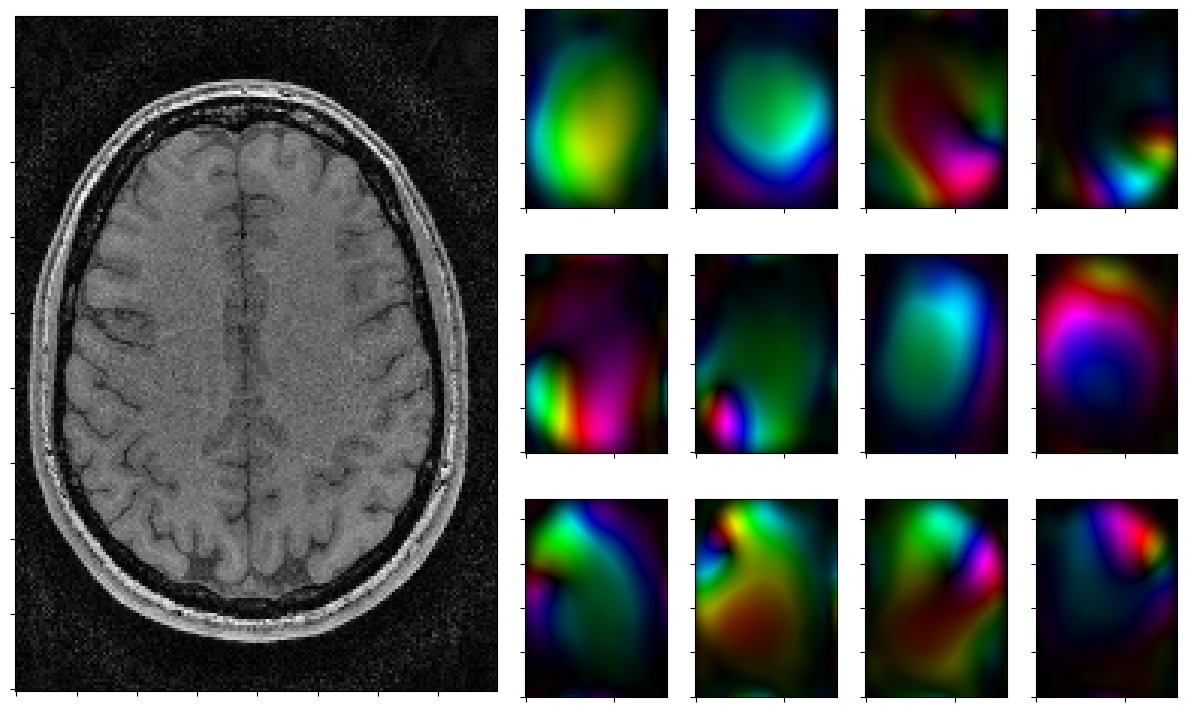

Run solver by hand and plot iterates

Run the solver iteratively and plot each step.

[12]:

for reco, reco_data in solver.while_(stoprule):

rho, coils = smoother.codomain.split(smoother(reco))

#rho, coils = normalize(rho,coils)

fig = plt.figure(figsize = (15,9))

gs = fig.add_gridspec(3,7)

axs = [fig.add_subplot(gs[0:3, 0:3])]

axs[0].imshow(np.abs(rho),cmap=mplib.colormaps['Greys_r'],origin='lower')

axs[0].xaxis.set_ticklabels([])

axs[0].yaxis.set_ticklabels([])

for j in range(3):

for k in range(3,7):

axs.append(fig.add_subplot(gs[j,k]))

axs[-1].xaxis.set_ticklabels([])

axs[-1].yaxis.set_ticklabels([])

for j in range(nrcoils):

axs[1+j].imshow(complex_to_rgb(coils[j,:,:]),origin='lower')

plt.show()

2026-01-29 15:10:07,969 INFO     CountIterations      :: it. 0>=5

2026-01-29 15:10:08,235 INFO     CombineRules         :: it. 0>=1000 | ((rel X:--(x=0)! | rel Y:--(y=0) ) & kappa:1.0e+00) | it. 0>=1000

2026-01-29 15:10:08,480 INFO     CombineRules         :: it. 1>=1000 | ((rel X:4.5e-02>=2.5e-01  | rel Y:1.0e-01>=2.5e-01 [Rule RelTolXStop(0.3333333333333333) triggered.Rule RelTolYStop(0.3333333333333333) triggered.]) & kappa:1.0e+00[All rules triggered.]) | it. 1>=1000

../_images/notebooks_parallel_mri_21_1.png